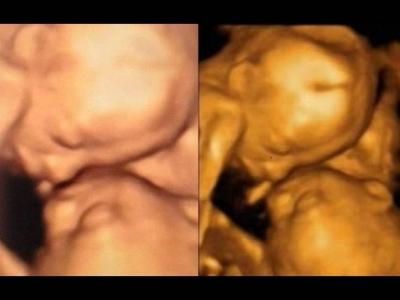

美国食品及药物管理局(FDA)警告拍3D超

FDA指,超声波测试应只用作医学用途,及由执业医护人员负责。 (神秘的地球报道...